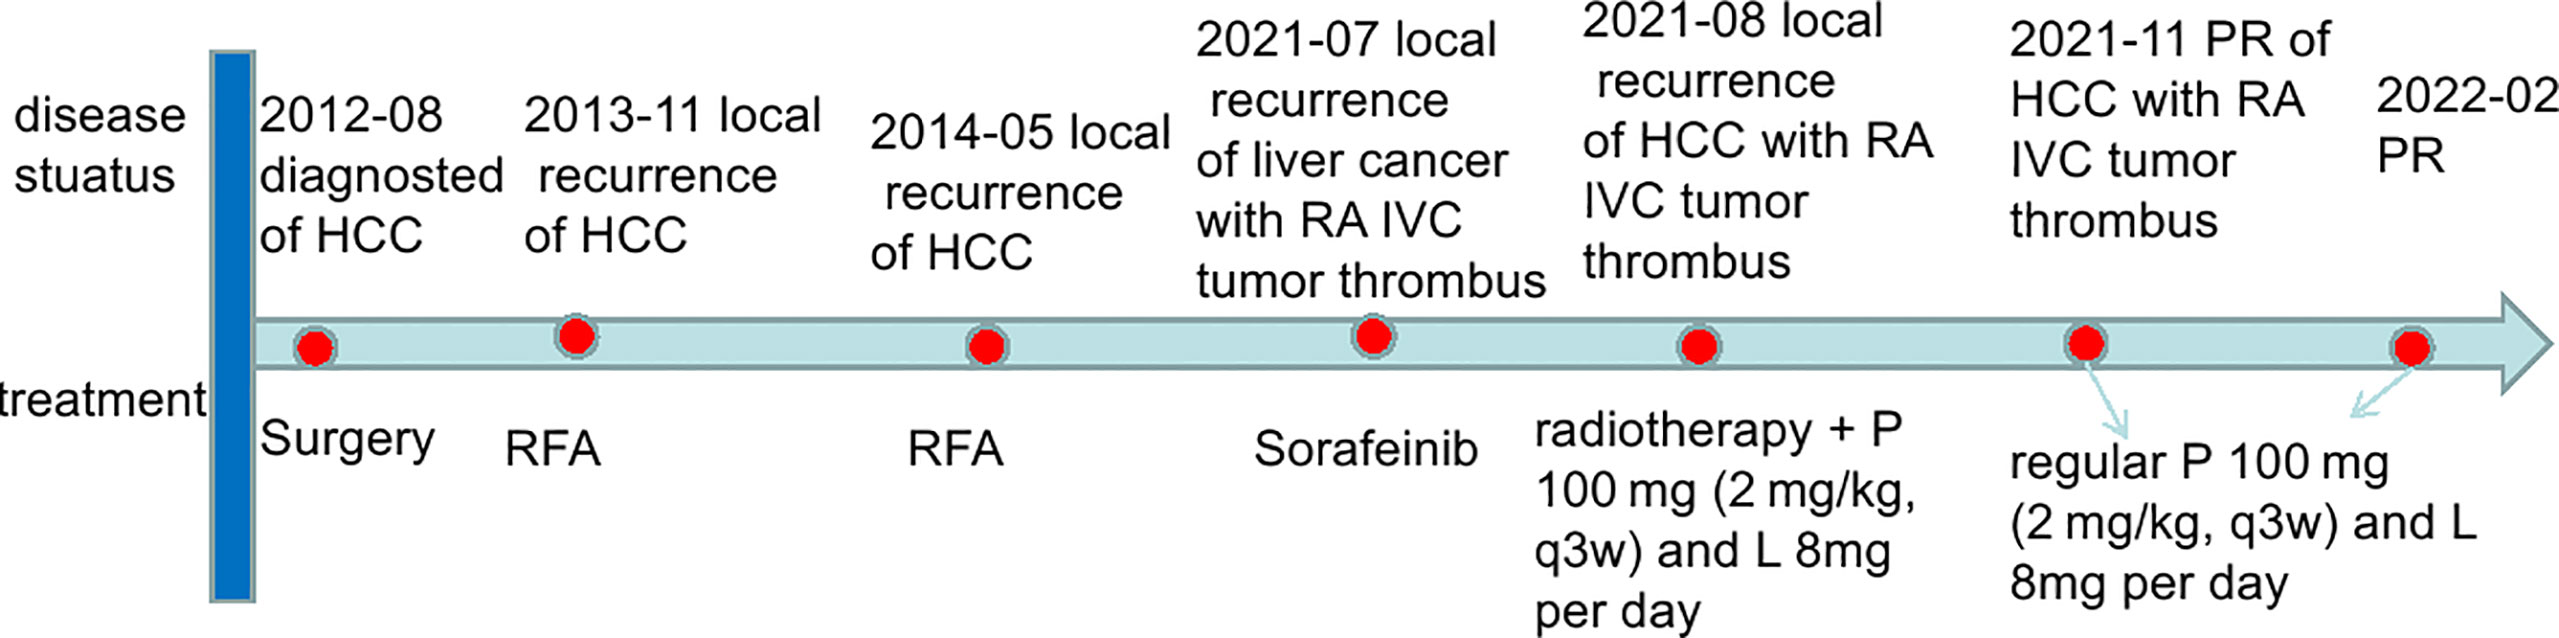

This case report was conducted per the CARE Guidelines (17). In July 2021, a 66-year-old Chinese woman was hospitalized due to severe bilateral lower extremity edema and palpitation, without any accompanying symptoms, such as abdominal pain or bloating. She had no history of high blood pressure, diabetes, or hepatitis. She had been diagnosed with HCC nine years ago and had undergone surgical resection. Postoperative pathology revealed a highly differentiated HCC. She had received radiofrequency ablation because of local HCC recurrence in November 2013 and May 2014. Subsequently, the patient did not undergo medical examination until July 2021. In July 2021, an enhanced computed tomography (CT) showed HCC recurrence at the junction of the anterior segment (S5/S8) of the liver, with approximately 1.8 × 1.4 cm size. The mass wrapped and invaded the adjacent IVC and grew into the IVC, RA, and left renal vein. The diagnosis was HCC with RA and IVC tumor thrombi with Barcelona clinic liver cancer (BCLC) stage-C (Figure 1). Then, the patient received sorafenib treatment and developed grade 4 (the US National Cancer Institute Common Terminology Criteria for Adverse Events [CTCAE v4.03]) skin rash and discontinued the sorafenib treatment. Hormones and proglobulin were used to treat dermatitis, and adverse skin reactions were reversed. According to a published study, radiotherapy can be used to treat liver cancer with RA and IVC tumor thrombi (18). Moreover, immunotherapy plus radiotherapy and antiangiogenic therapy is a safe and effective approach for advanced HCC (19). Therefore, we administrated radiotherapy, immunotherapy, and lenvatinib. The patient received radiotherapy in August 2021 through volumetric modulated arc therapy and respiratory gating technology. The dose for HCC recurrence was 50 Gy/25 fractions and for HCC with RA and IVC tumor thrombi was 45 Gy/25 fractions (Figure 2). She simultaneously received pembrolizumab (100 mg; 2 mg/kg, q3w) and lenvatinib (8 mg/day). Lower extremity edema and palpitations resolved after radiotherapy. Toxicity was well tolerated with no liver toxicity, and grade ≥ 3 adverse events were observed. After four cycles of pembrolizumab plus lenvatinib treatment, the CT scan indicated that the patient had a partial response and a decreased thrombus according to the Response Evaluation Criteria in Solid Tumors (RECIST) v.1.1. The HCC lesion at the junction of S5/S8 segment disappeared, and the IVC/RA thrombus decreased in size (Figure 3). No disease progression was observed. The patient continued to receive the pembrolizumab plus lenvatinib treatment (the last pembrolizumab treatment day was March 26, 2022). The patient remained stable at the time of writing (> 7 months). During the treatment period, there was no grade ≥ 3 adverse events or liver toxicity. Leukopenia (grade 2), thrombocytopenia (grade 1), hypoalbuminemia (grade 1), and hypertension (grade 2) were resolved using symptomatic drug treatment. Granulocyte colony-stimulating factor was administered to deal with white blood loss. A CT scan was regularly performed for every 3 months. Blood routine, liver function, kidney function, electrolyte, thyroid function, and pituitary function were regularly measured. The timeline scheme of the major clinical events of the patient since HCC diagnosis is shown in Figure 4.

Figure 4 The timeline scheme of the major clinical events of the patient since diagnosis. HCC, hepatocellular carcinoma; IVC, inferior vena cava; RA, right atrium; RFA, radiofrequency ablation; P, pembrolizumab; L, lenvatinib; PR, partial response.